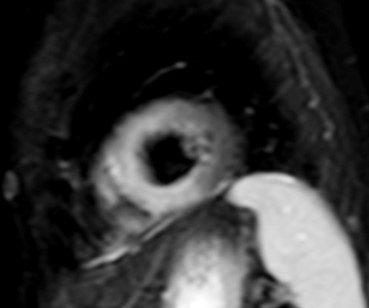

CMR can detect myocardial ischemia using either vasodilator perfusion stress testing (adenosine/dypiridamole/regadenoson) or dobutamine stress testing. The most commonly employed test in clinical practice is adenosine stress perfusion, due to its rapid implementation and favorable side effect profile compared with dobutamine. In contrast to other imaging modalities, adenosine stress perfusion CMR has no imaging limitations depending on body dimensions or operator experience. For these reasons, it is the ideal modality for the assessment of both macro- and micro-vascular coronary artery disease, specifically in patients who are unable to exercise, as often occurs amongst patients with systemic autoimmunity [11] (Fig. 2).

Fig. 2.

Fig. 2.Stress CMR perfusion. Adenosine stress perfusion CMR showing a perfusion defect in the inferolateral wall in a patient with systemic sclerosis and ventricular arrhythmias. CMR, cardiovascular magnetic resonance imaging.